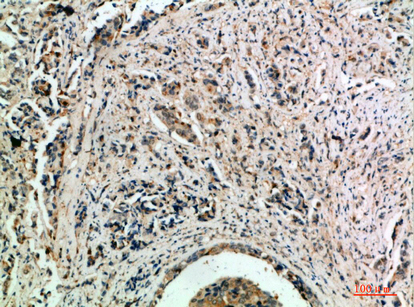

TLE1/2/3/4 (Transducin-Like Enhancer of Split 1/2/3/4) antibodies target members of the TLE protein family, which function as transcriptional corepressors involved in developmental regulation and oncogenesis. These proteins are homologs of Drosophila Groucho, sharing a conserved N-terminal Q domain and WD40 repeats for protein interactions. TLE proteins lack DNA-binding domains but modulate gene expression by interacting with transcription factors like HES1. RUNX, and TCF/LEF, thereby regulating Notch, Wnt, and other signaling pathways. Their roles span cell differentiation, apoptosis, and epigenetic regulation via histone deacetylase (HDAC) recruitment.

In diagnostics, TLE1 is a well-established immunohistochemical marker for synovial sarcoma, with nuclear staining aiding its distinction from other soft tissue tumors. TLE2 and TLE4 are less characterized but implicated in hematopoiesis and immune responses. TLE3 has gained attention in oncology for its potential association with chemotherapy response, particularly in gynecological cancers, though evidence remains inconclusive. Commercially available antibodies vary in specificity; cross-reactivity between TLE isoforms is a common challenge, necessitating careful validation in research and clinical settings. Recent studies also explore TLE dysregulation in neurodegenerative diseases, expanding their therapeutic relevance.